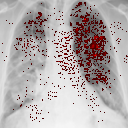

II.6 Saliency maps

Saliency maps assign pixels in an image according to their contribution (a class score derivative) to the final output of a CNN-based classifier. Another interpretation of saliency maps is that the magnitude of the derivative indicates which pixels need to be changed the least to affect the class score the most Simonyan et al. (2014). A saliency map is extracted for a given image and class label by back-propagation procedure. This technique helps extract information from the black box model and visualise how it interprets the given data. Saliency maps are one of the essential tools that allow verifying that classification results do not depend on artefacts from the training set, so-called "shortcuts", and help in understanding where observed misclassifications come from Alqaraawi et al. (2020). Saliency maps for instance can be utilised to identify whether the classification of COVID-19 is based on the infected regions of the lungs, rather than being influenced by image artefacts such as drains or specific body positioning for the X-ray scan.

To better illustrate the most important features of analysed samples in the view of the two considered CNN classifiers a state-of-the-art AI-explainable approach known as Image-Specific Class Saliency Simonyan et al. (2014) is applied. The maps are obtained for the most accurate model: EfficientNet-B0 trained on the balanced dataset (Results). To denoise the results and make them more readable the top 10 most valuable features were marked on the source image.

To validate that results are not biased by models focusing on non-biomarkers saliency maps are used. The regions of interest of correctly TOP-1 predicted class on the representative test images are shown in Fig. 12. It is clear that the saliency maps often indicate the lung region as important, moreover, they do not concentrate on artificial indicators like the drain visible in Fig. 12d. That suggests that the model takes into account genuine lung lesions.

We successfully validated that the models did not learn so-called "shortcuts" using saliency maps. However, the model returns some areas of concern, especially in normal and viral pneumonia classes. The CNN focuses on the lower parts of the lungs and body parts behind them like a diaphragm, which is definitely not a bio-indicator in this case. Some of the indicated features can be seen under armpits, a similar result to saliency maps obtained by DeGrave et al. DeGrave et al. (2021). While such effects could indicate that CNN has learned to recognise "shortcuts", the majority of the attention is focused in the lungs area as one would expect. To verify this is not a significant effect maps for misclassified images are analysed (Figs. 12e and 12e), e.g image for COVID-19 positive case classified as normal. No obvious differences from properly classified images are observed. While the CNNs locate the most important features in the lung area as expected they do not yield straight human interpretable imaging biomarkers. This highlights the still inseparable black-box limitation of the deep learning algorithms.